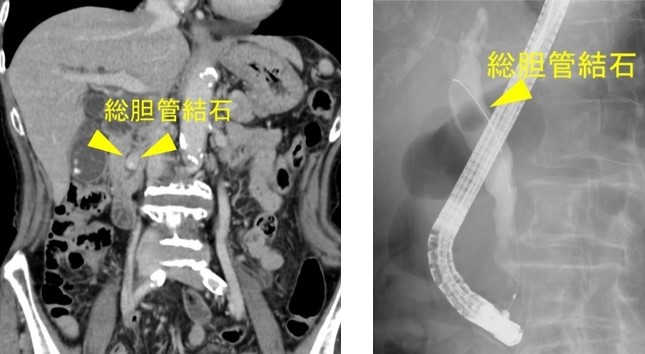

内視鏡的逆行性胆管膵管造影 (ERCP) および磁気共鳴胆管膵管造影 (MRCP) は医療検査です。以下のような胆管や膵管の問題を診断するために使用されます。

ERCP では、内視鏡と X 線を使用して管の画像を作成します。これは、胆汁および膵臓の問題を診断するための標準的な方法です。しかし、それは侵襲的であり、さまざまな合併症を伴います。

ERCP では、先端に小さなカメラが付いた長い管である内視鏡とカテーテルを使用します。どちらのツールも小腸に挿入されます。 ERCP には、放射線を使用して管の画像を作成するX 線も含まれます。

ERCP を使用すると、医師は次のような特定の治療を完了することもできます。

- 石の除去